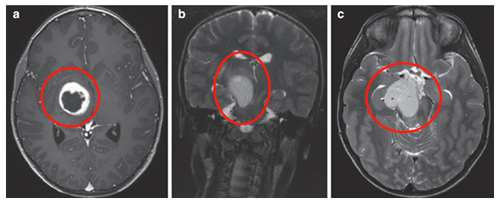

3岁患儿因呕吐和巨脑畸形就诊。CT及MRI检查显示右侧丘脑病变伴钙化及第三脑室后部梗阻,引发脑积水。

在8岁、11岁和13岁时,James T. Rutka教授通过第三脑室内窥镜切开术成功治疗脑积水,影像显示肿瘤增大伴多发囊肿形成,并逐渐出现左上肢震颤。

13岁时进行神经导航和超声引导下活检,确诊为WHO I级毛细胞星形细胞瘤。随着肿瘤囊肿持续扩大,患儿出现急性偏瘫症状。

超声引导下将Ommaya导管和储液囊置入肿瘤囊性部分。术后MRI显示囊性占位解除,脑室形态逐渐恢复正常。四个月后,因偏瘫症状未改善,行经胼胝体半球间入路肿瘤次全切除术。术后偏瘫改善,患儿生长和智力发育正常,近期随访显示肿瘤无复发。免疫组化检测显示RAFV600E突变阴性,H3K27M阴性。